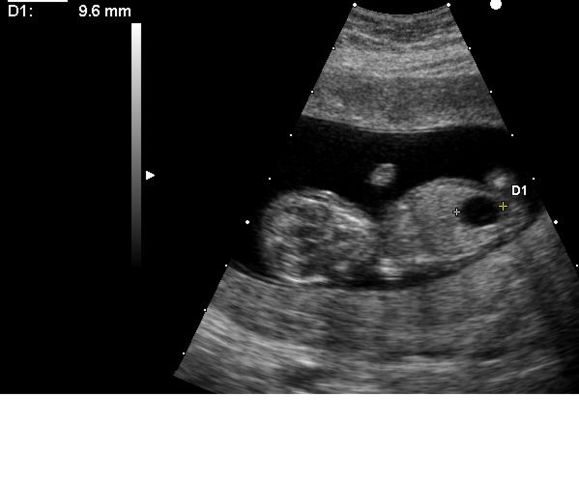

Méga vessie chez un embryon porteur d'une trisomie 21.Megacystis in embryo with Down'syndrome. . |